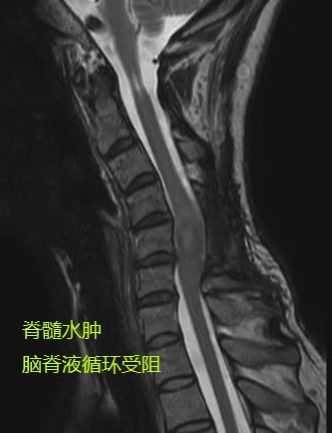

患者来院时四肢肌力4级,搀扶才能站立,其中左上肢精细运动变差。

周迎春教授考虑到患者不仅有椎管内外占位的问题,还合并脊柱畸形,而要完整切除肿瘤必须打开左侧椎间孔,将使得脊柱畸形进一步加重,于是为患者制定了前后路联合手术方案:切除肿瘤+脊柱矫形。

经后路切除椎管及椎间孔肿瘤,给肿瘤“除根”,为脊髓“减负”。